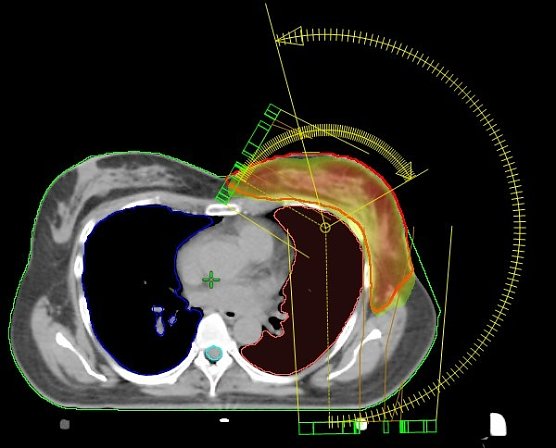

Die seit dem Jahr 2009 im Südharz Klinikum eingesetzte Bestrahlungstechnik an den Linearbeschleunigern macht es möglich, den Bereich der Bestrahlung nicht nur geradlinig, sondern auch bogenförmig maßgeschneidert zu erfassen.

Wir bestrahlen die Brust nicht standardisiert, sondern programmieren die Technik so, dass der Dosisverlauf individuell an die jeweilige Brust angepasst wird. Und das ist von Frau zu Frau immer unterschiedlich. Kollateralschäden an benachbarten Organen werden so auf ein Minimum reduziert”, berichtet der leitende Medizinphysiker Dirk Strauß.

Einzigartig in Nordhausen: VMAT-Bewegungsbestrahlungstechnik mit 2 Bögen (Nordhäuser Standardtechnik); der Hochdosisbereich erfasst ausschließlich das Zielvolumen und die umgebenden Risikoorgane werden geschont.